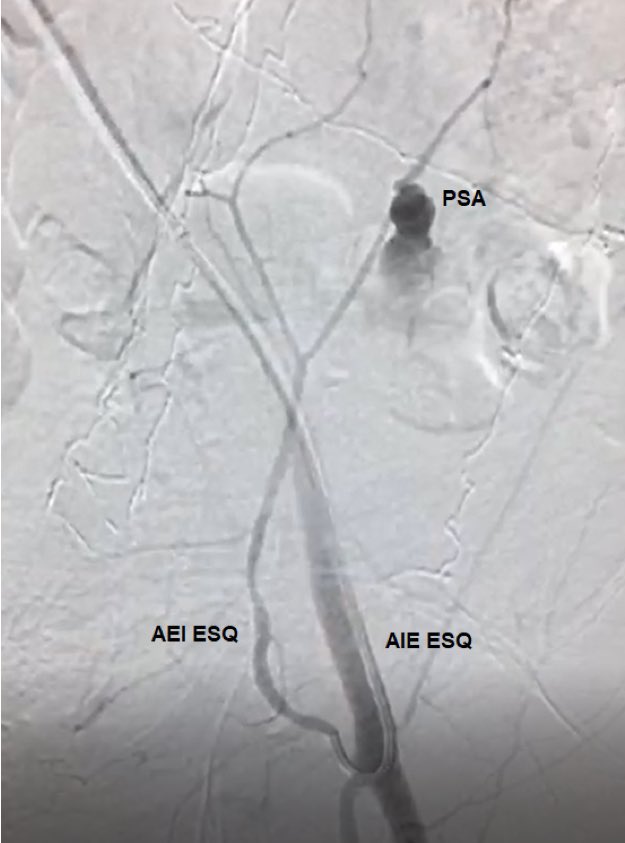

Embolization of the inferior epigastric artery in a huge abdominal wall hematoma caused by paracentesis in a patient with liver cirrhosis.

#MedTwitter